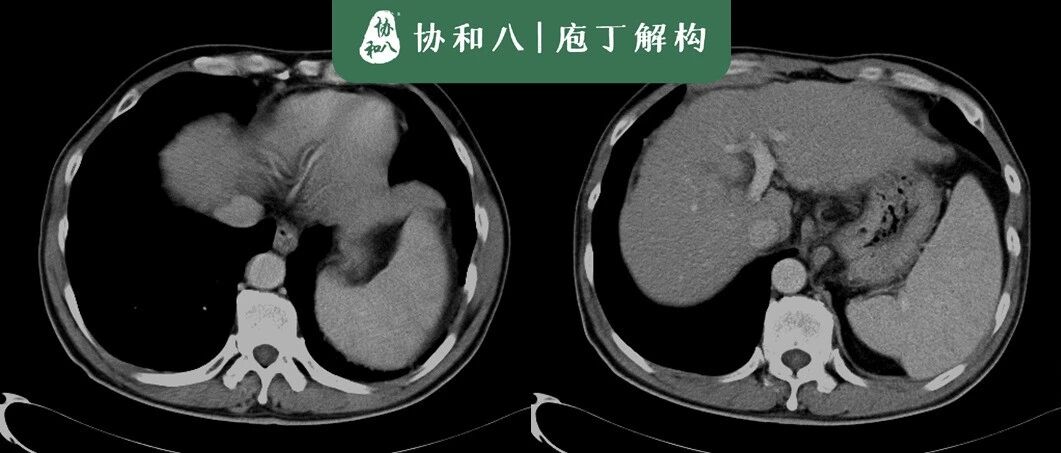

腹腔里的牛刀小试 | 协和八

来源:协和八